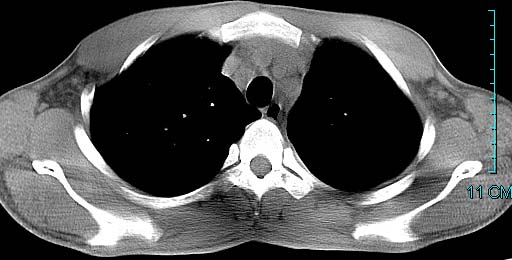

以下是引用ctkz987在2006-3-28 13:04:00的发言:[br]左侧胸腔积液穿刺后多发气液平(多房性),结合临床有高热不除外合并感染。

以下是引用qian在2006-3-28 14:32:00的发言:[br]左肺下叶大片状阴影,密度不均,见有条片影和空洞及气液平,少量胸腔积液伴有胸膜增厚,从图像看积液密度比水的密度高,结合病史,考虑左下肺化脓性炎症伴有脓胸。

以下是引用wawaquan在2006-3-28 22:25:00的发言:[br]左上肺舌段多发斑片影。结合“男24y咳嗽咳痰气促伴高热(38.5--39.5)20多天”及穿刺史,[br]考虑1 左下肺化脓性炎症;2脓胸。

以下是引用乡医在2006-3-28 18:37:00的发言:[br]左侧多发液气平面结合患者男24y咳嗽咳痰气促伴高热(38.5--39.5)20多天,查胸水:ldh239.3,总蛋白59.19,tb-ab阴性,利凡它试验+,红c2.7*109,白c1.08*109,分类淋巴92%分叶8%,考虑1脓胸2肺隔离征感染